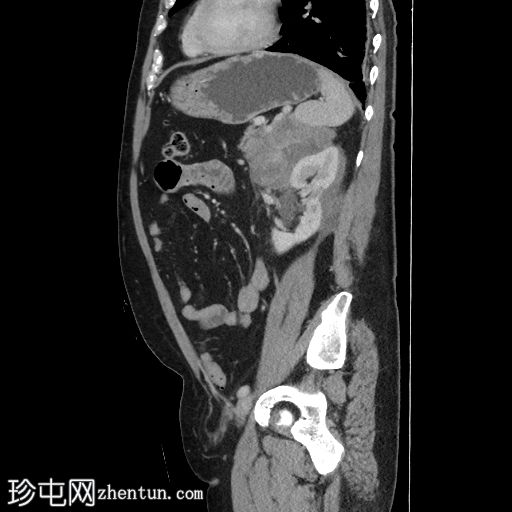

冠状位增强扫描(门静脉期)

右肾可见不规则分叶状低密度浸润性病变,超出肾包膜,并与右肝下叶相邻。

左肾可见弥漫性浸润性病变,以上极为中心。左肾浸润性病变与胰尾相邻,胰尾可能受累,表现为胰腺后缘不规则、脂肪间隙消失。此外,浸润性病变与左侧肾上腺外侧肢相邻。

左肾偶然发现一小结石和肾囊肿。

脾脏下极可见一密度不明、呈分叶状/浸润性改变的肿块。

本例为肾淋巴瘤,具体为弥漫性大B细胞淋巴瘤(DLBCL)。

鉴于其浸润性病变,高度怀疑为淋巴瘤。原发性肾脏恶性肿瘤(例如肾细胞癌、肾嗜酸细胞瘤)的可能性较小。肾脏肿块活检证实为肾脏DLBCL。